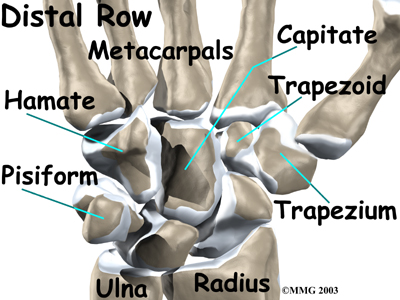

is where the wrist creases when you bend it. Beginning with the thumb-side of the wrist, the proximal row of carpal bones is made up of the scaphoid, lunate, and triquetrum. The second row of carpal bones, called the:

meets the proximal row a little further toward the fingers. The distal row is made up of the trapezium, trapezoid, capitate, hamate, and pisiform bones.

As its name suggests, the ulnar collateral ligament (UCL) is on the ulnar side of the wrist. It crosses the ulnar edge (the side away from the thumb) of the wrist. It starts at the ulnar styloid, the small bump on the edge of the wrist (on the side away from the thumb) where the ulna meets the wrist joint. There are two parts to the cord-shaped UCL. One part connects to the pisiform (one of the small carpal bones) and to the transverse carpal ligament, a thick band of tissue that crosses in front of the wrist. The other goes to the triquetrum (a small carpal bone near the ulnar side of the wrist). The UCL adds support to a small disc of cartilage where the ulna meets the wrist. This structure is called the triangular fibrocartilage complex (TFCC) and is discussed in more detail below. The UCL stabilizes the TFCC and keeps the wrist from bending too far to the side (toward the thumb).

The radial collateral ligament (RCL) is on the thumb side of the wrist. It starts on the outer edge of the radius on a small bump called the radial styloid. It connects to the side of the scaphoid, the carpal bone below the thumb. The RCL prevents the wrist from bending too far to the side (away from the thumb).

The travels through a separate tunnel, called Guyon's canal. This tunnel is formed by two carpal bones (the pisiform and hamate), and the ligament that connects them.

The travels through a separate tunnel, called Guyon's canal. This tunnel is formed by two carpal bones (the pisiform and hamate), and the ligament that connects them.

After passing through the canal, the ulnar nerve branches out to supply feeling to the little finger and half the ring finger.

Branches of this nerve also supply the small muscles in the palm and the muscle that pulls the thumb toward the palm.